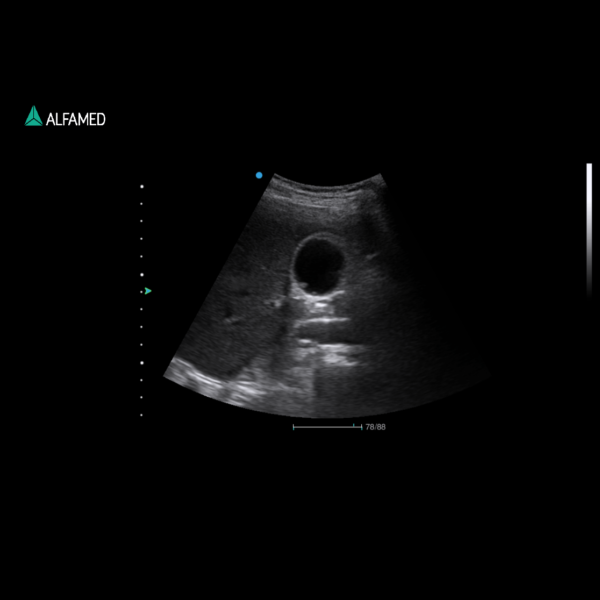

⦁ Modo B, 2B, 4B, M, Power Doppler Direcional, CW, M, PW; B/M, CFM, B/C,

PWD, CPA, DPA, B+CFM, B+CPA, B+DPA, B+PW, B+CFM+PW, B+CPA+PW,

Triplex/Duplex;

⦁ Modo B: área, circunferência, estenose, ângulo, volume, distância, função VE e outras;